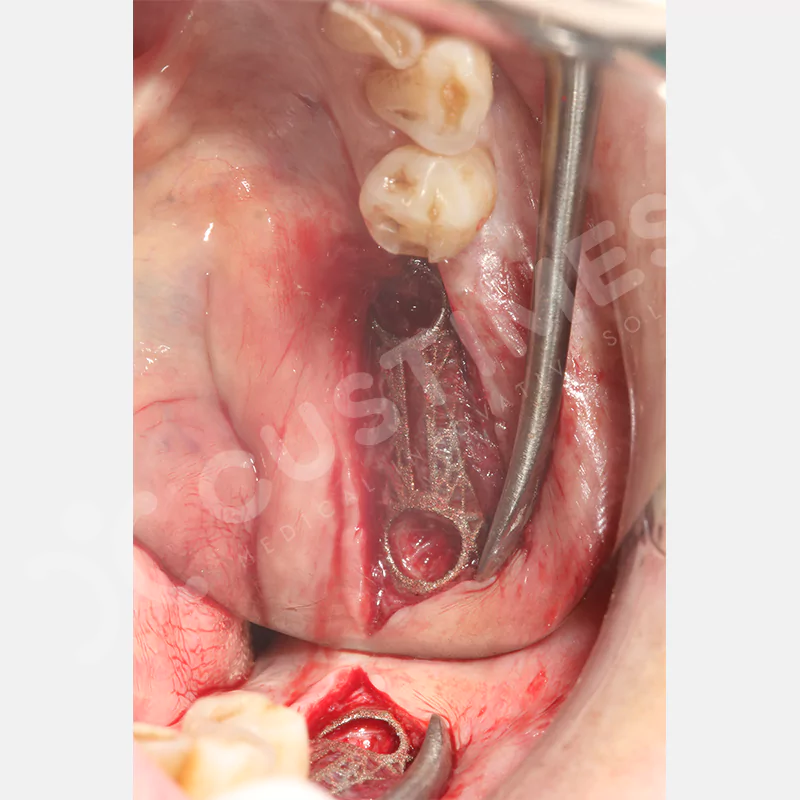

Dental implant uygulanamayan hastalarda kemik rejenerasyonunu sağlamak üzere geliştirilen kişiye özel titanyum mesh, kemik augmentasyon işlemlerinde greft materyalinin korunması ve yeni kemik oluşumunun desteklenmesi amacıyla kullanılan, hastanın kendi anatomisine tam uyumlu titanyum bir bariyer sistemidir.

Medikal sınıf titanyumdan, hastanın bilgisayarlı tomografi verileri kullanılarak CAD yazılımlarıyla tasarlanan ve 3D baskı teknolojisiyle üretilen bu yenilikçi çözüm, özellikle kompleks kemik defektlerinde standart meshlerin sağlayamadığı üstün mekanik stabilite ve mükemmel adaptasyon özellikleri sunar. Anatomik yapıya tam uyum sağlayarak greft materyalinin yerinde kalmasını garanti ederken, optimal vaskülerizasyonu destekleyerek kemik rejenerasyon sürecini hızlandırır.